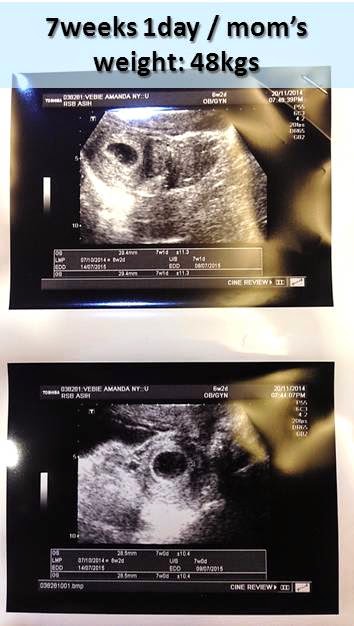

I've been meaning to share my pregnancy progress with you few months ago, but I hesitated because I thought it was to early for me to do so.

Now I'm more comfortable to share my pregnancy progress, as I've passed the first two-trimesters..

Back to my pregnancy progress..

I'm now at the end of my 27th week, so..

My baby's development from time to time is as following...

My own development is as following..

Up until today I...

• have gained almost 7 kgs and my baby's weight has reached 1 kg  :)